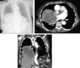

Large unilateral intrathoracic mass